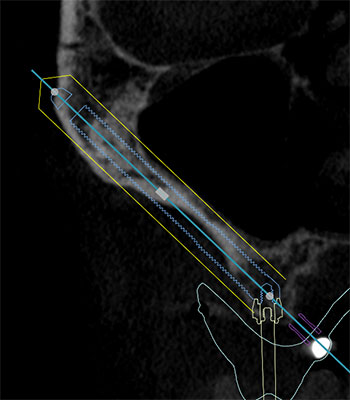

ザイゴマインプラント(右上6相当部位)

ザイゴマインプランのポジションは患者さんの顔面骨の解剖学的なにより異なります。ザイゴマインプラントも通常のインプラント治療と同様外科主導で行うべきではなく、補綴主導でありより低侵襲でなければなりません。

1995年にBrånemarkが開発した頬骨に向かって埋入される長いインプラントです。高度に骨吸収した上顎臼歯部に対するインプラント治療としては、サイナスフロアエレベーションや骨移植等の付加的な骨造成処置(グラフト)を行う治療と、骨造成の代替としてショートインプラント、傾斜埋入、ザイゴマインプラントなどを適応する(グラフトレス)治療に大別されます。グラフトを選択した場合は多くの場合、即時荷重を行う事が出来ず、治療期間が長くなる事や、術後の骨吸収等のデメリットが考えられます。ザイゴマインプラントを使用したグラフトレス治療を行う事で、即時荷重が可能となりますが、本法は高度な治療技術を必要とします。また術後の感染リスクを考慮した上で慎重に選択すべき治療です。Dr橋村は、2010年よりザイゴマインプラント治療を行い、独自の改良を加え、術後の感染リスクを抑えたより安全性の高いザイゴマインプラント治療を行なっております。適応に際しては正確な埋入ポジションおよび角度が要求されるため、All-on-4 Clinic では、DTX studio™ implantを用いて治療計画立案、安全な埋入手術を行う事で、患者さんにとってインプラント及び補綴物を永く快適に使用していただける事が出来ます。

※画像2枚目:左上から時計回りに、右上3相当部位 → 正中相当部位 → 左上5相当部位 → 左上6相当部位